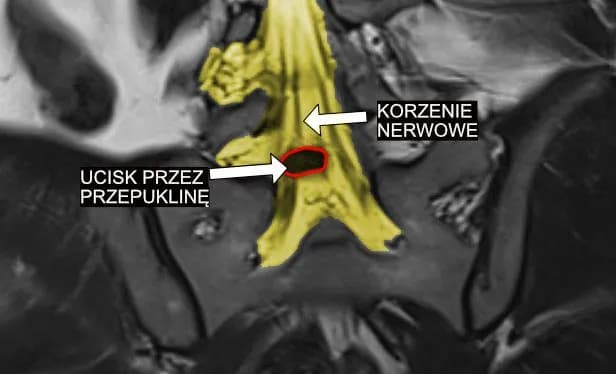

Tag icd-10 g54